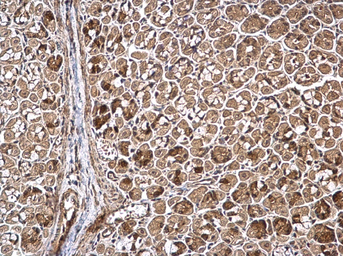

WWP1 antibody detects WWP1 protein at cytoplasm by immunohistochemical analysis.

Sample: Paraffin-embedded human breast carcinoma.

WWP1 stained by WWP1 antibody (GTX110872) diluted at 1:500.

Antigen Retrieval: Citrate buffer, pH 6.0, 15 min